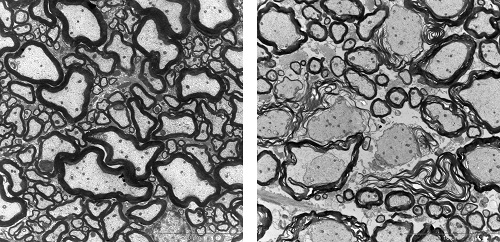

Milch kann MS-Symptome verstärken2. März 2022 Foto: © Knut Wiarda – stock.adobe.com Menschen mit Multipler Sklerose klagen nach dem Konsum von Milchprodukten oft über stärkere Krankheitssymptome. Forschende der Universitäten Bonn und Erlangen-Nürnberg haben nun einen möglichen Grund dafür gefunden. Demnach kann ein Protein der Kuhmilch Entzündungen auslösen, die sich gegen die Isolierschicht um die Nervenzellen richten. Auslöser der Studie waren Berichte von MS-Patientinnen und -Patienten: „Wir hören immer wieder von Betroffenen, dass es ihnen schlechter geht, wenn sie Milch, Quark oder Joghurt zu sich nehmen“, erklärt Stefanie Kürten vom Anatomischen Institut des Universitätsklinikums Bonn. „Uns interessiert die Ursache für diesen Zusammenhang.“ Die Professorin für Neuroanatomie gilt als Expertin für Multiple Sklerose. Mit der Studie begannen sie 2018 an der Universität Erlangen-Nürnberg. Vor anderthalb Jahren wechselte sie nach Bonn, wo sie die Arbeiten zusammen mit ihrer Arbeitsgruppe fortsetzte. „Wir haben Mäusen verschiedene Proteine aus der Kuhmilch injiziert“, sagt sie. „So wollten wir herausfinden, ob es einen Bestandteil gibt, auf den sie mit Krankheitssymptomen reagieren.“ Tatsächlich wurden die Forschenden fündig: Wenn sie den Tieren den Kuhmilch-Inhaltsstoff Casein zusammen mit einem Wirkverstärker verabreichten, entwickelten die Mäuse danach neurologische Störungen. Unter dem Elektronenmikroskop zeigte sich, dass bei ihnen die Isolierschicht um die Nervenfasern geschädigt war. Durchlöcherte Myelinschicht „Als Grund vermuteten wir ähnlich wie in MS-Patienten eine fehlgeleitete Immunreaktion“, erklärt Rittika Chunder, die in der Arbeitsgruppe von Kürten habilitiert. „Die körpereigene Abwehr attackiert eigentlich das Casein, zerstört dabei aber auch Proteine, die an der Bildung des Myelins beteiligt sind.“ Zu einer solchen Kreuzreaktivität kann es kommen, wenn sich zwei Moleküle zumindest in Teilen sehr ähneln. „Wir haben das Casein mit verschiedenen Molekülen verglichen, die für die Produktion von Myelin wichtig sind“, sagt Chunder. „Dabei sind wir auf ein Eiweiß namens MAG gestoßen. Es sieht dem Casein in manchen Bereichen ausgesprochen ähnlich – so sehr, dass bei den Versuchstieren die Antikörper gegen Casein ebenfalls gegen MAG aktiv waren.“ Bei gesunden Mäusen (li.) schmiegt sich das isolierende Myelin (schwarz) als kompakte Schicht eng um die Nervenfasern, die Axone. Bei Mäusen, denen Casein injiziert wurde (r.), lockert sich die Struktur des Myelins auf. Es umhüllt die Axone nur noch lose. Manchmal fehlt die Isolierschicht sogar ganz. (Fotos: AG Prof. Kürten/Uni Bonn) In den Casein-behandelten Mäusen richtete sich die körpereigene Abwehr also auch gegen MAG, wodurch das Myelin destabilisiert wird. Doch inwieweit lassen sich die Ergebnisse auf Menschen mit MS übertragen? Um diese Frage zu beantworten, gaben die Forschenden Casein-Antikörper von Mäusen zu menschlichem Hirngewebe. Tatsächlich reicherten sie sich dort an den Zellen an, die im Gehirn für die Myelin-Produktion verantwortlich sind. Selbsttest auf Antikörper gegen Casein Für die Antikörperproduktion sind die B-Zellen verantwortlich. Die B-Zellen im Blut von MS-Kranken sprechen der Studie zufolge besonders stark auf Casein an. Vermutlich haben die Betroffenen irgendwann durch den Konsum von Milch eine Allergie gegen Casein entwickelt. Sobald sie nun Frischmilchprodukten zu sich nehmen, stellt das Immunsystem daher massenhaft Casein-Antikörper her. Diese schädigen aufgrund der Kreuzreaktivität mit MAG auch die Myelinschicht um die Nervenfasern. Davon sind allerdings nur MS-Kranke betroffen, die gegen Kuhmilch-Casein allergisch sind. „Wir entwickeln momentan einen Selbsttest, mit dem Betroffene überprüfen können, ob sie entsprechende Antikörper in sich tragen“, sagt Kürten, die auch Mitglied im Exzellenzcluster ImmunoSensation2 ist. „Zumindest diese Subgruppe sollte auf den Konsum von Milch, Joghurt oder Quark verzichten.“ Möglicherweise erhöht Kuhmilch auch bei Gesunden das Risiko, an MS zu erkranken. Denn auch bei ihnen kann Casein Allergien auslösen – das ist den Forschenden zufolge vermutlich gar nicht einmal so selten. Sobald eine solche Immunantwort besteht, kann es theoretisch zu einer Kreuzreaktivität mit dem Myelin kommen. Das bedeute allerdings nicht, dass sich bei einer Überempfindlichkeit gegen Casein zwangsläufig eine MS entwickle, betont die Professorin. Dazu seien vermutlich noch weitere Risikofaktoren erforderlich. Beunruhigend sei dieser Zusammenhang dennoch, meint Kürten: „Studien zufolge sind die MS-Zahlen in Bevölkerungsgruppen erhöht, in denen viel Kuhmilch konsumiert wird.“